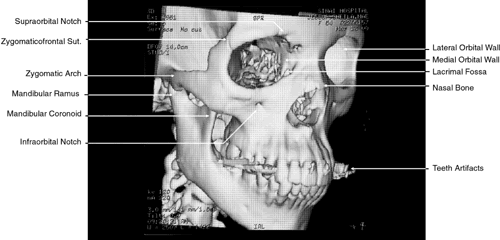

More recently, evolution in CT software has permitted the creation of high-resolution 3D images (Fig. 1).8 This has been of particular interest in cases of traumatic and congenital bony defects of the skull, where such images are quite useful in planning reconstructive efforts. With additional mathematical manipulation of the attenuation coefficients obtained from cross-sectional 2D slices, 3D images can be reconstructed. This is accomplished by estimating the interstice voxel HU values. These are generally assumed to be a weighted average of the HU values for the voxels of the two adjacent slices. The locations of the voxels are then described in terms of a 3D coordinate system with the z-axis parallel to the CT scanner table, the y-axis perpendicular to the top of the table, and the x-axis parallel to the CT scanner gantry opening. These images can then be reconstructed in either gray-scale or false color and recorded on film or tape.

Fig. 1. Three-dimensional computed tomography reconstruction of facial bones and orbit.

The globe is shown in Figure 12. The orbit and periorbital structures are shown in Figures 13 through 16, and the optic canal is shown in Figures 17 through 26. The cavernous sinus and optic chiasm are shown in Figures 27 and 28, and the posterior visual pathway and cranial nerves are shown in Figures 29 through 33.

Fig. 13. Three-dimensional reconstruction of orbit and infraorbital structures (Water's view).

Fig. 14. Three-dimensional reconstruction of orbit (anterior view).